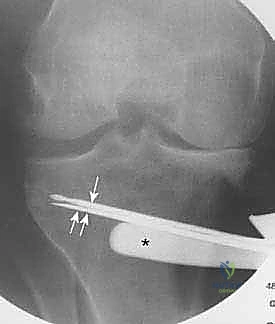

تُعد الأشعة السينية (X-rays) الممتدة من الحوض إلى الكاحل (Scanogram) ضرورية جداً لحساب زاوية التقوس بدقة وتحديد مقدار التعديل المطلوب جراحياً.

قبل العملية، يتم قياس زوايا الركبة بدقة متناهية. كل درجة من درجات التعديل يتم حسابها مسبقاً.

استخدام التخطيط الرقمي يضمن عدم حدوث تصحيح مفرط (Over-correction) أو تصحيح ناقص (Under-correction)، وهو ما يميز الجراح الخبير عن غيره.